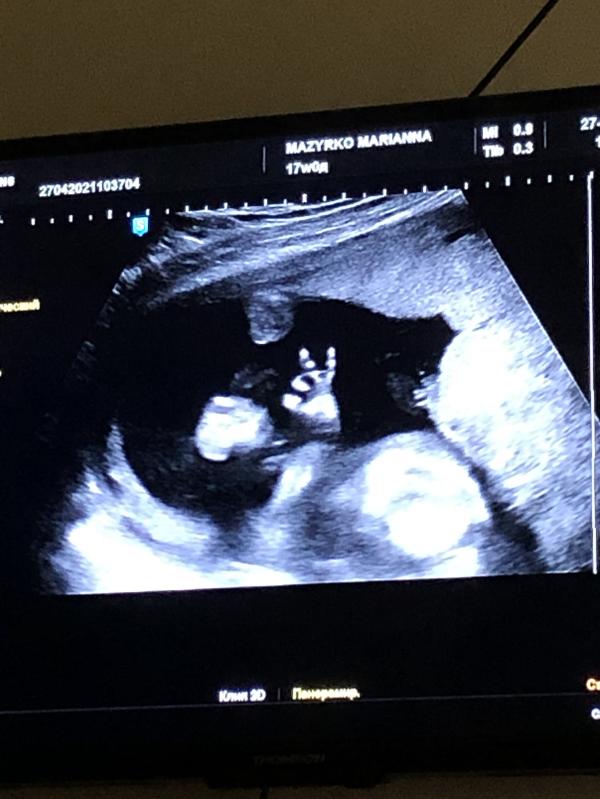

С первой секунды,Марианна Александровна увидела нашего мальчика. Показала нам, «то самое» пикантное место)))У мужа не осталось сомнений)) 100% boy💙

p.s. На третьем фото у нашего парня все 👌🏻))))